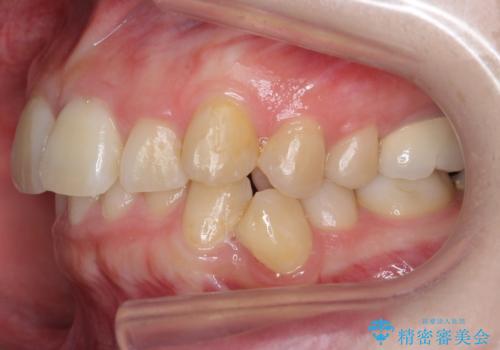

- 前歯の並びと下の歯のがたつきを主訴に来院。

左下にがたつきが集中していました。

歯を抜かずに、左上および左下の奥歯を後ろに送ることで隙間を確保しました。

左下の第一小臼歯が歯列からはみ出て、近心傾斜しており、抜歯の上ワイヤー矯正の選択肢もお話ししましたが、非抜歯で、インビザライン矯正を希望されました。左下の第一小臼歯は完全に並べることは難しいと初めから説明し、納得いただいた上で治療開始しました。